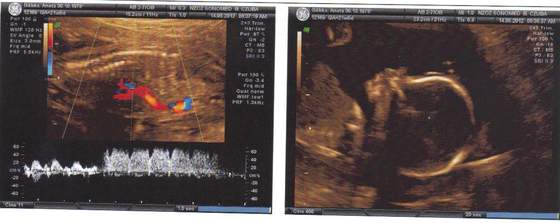

Dzisiejsze foto malenkiej:-)

Ja juz po wizycie z dzidziusiem wszystko ok wszystkie wymiary ok idealnie do tygodnia ciazy serduszko nerki itp wszystko ok :-DI bedzie DZIEWCZYNKA:-D:-D jednak moje wczesnociazowe przeczucie( zanim zaczeli mi chłopaka wmawiac) sie spełniło ,malutka wazy 475 9 .Tylko jest mały problem łozysko jest nisko:eek: co prawda lekarka powiedziała ze na tylnej scianie i to ok,ale jest nisko podobno moze sie podniesc jeszcze zobaczymy .